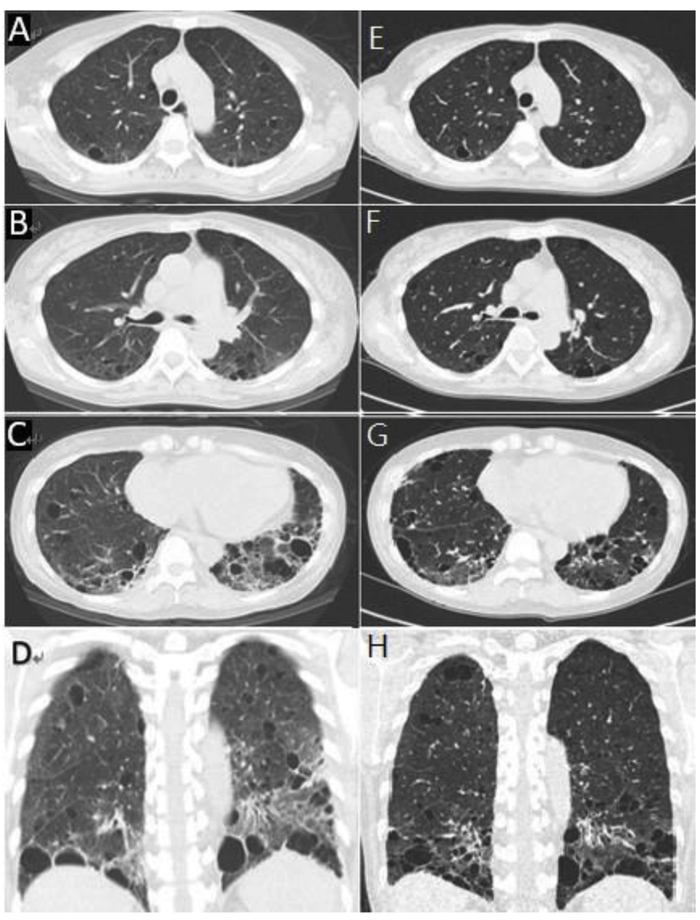

2008年,胸部X线片未见明显异常(图1A)。

图1 A、B、C分别为2008、2015及2016年胸部X线对比

胸片示:除了左下叶实变外,双侧弥漫性线状和网状浸润影,散在细小的囊性病变(图1B)。

2016年1月,复查胸片显示左肺下叶实变明显消退,但双侧肺实质内持续存在囊性病变和网状浸润(图1C)。